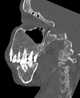

Congenital prognathism